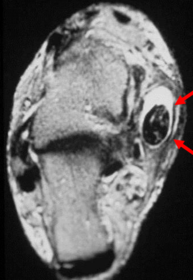

| What does this indicate? | Increased signal and enhancement of the soft tissue plantar to the proximal phalanx suggestive of subcutaneous infection without abscess |

| What does this indicate? | Increased signal and soft tissue distension dorsally representing subcutaneous abscess communicating with associated with plantar ulcerative defect. |